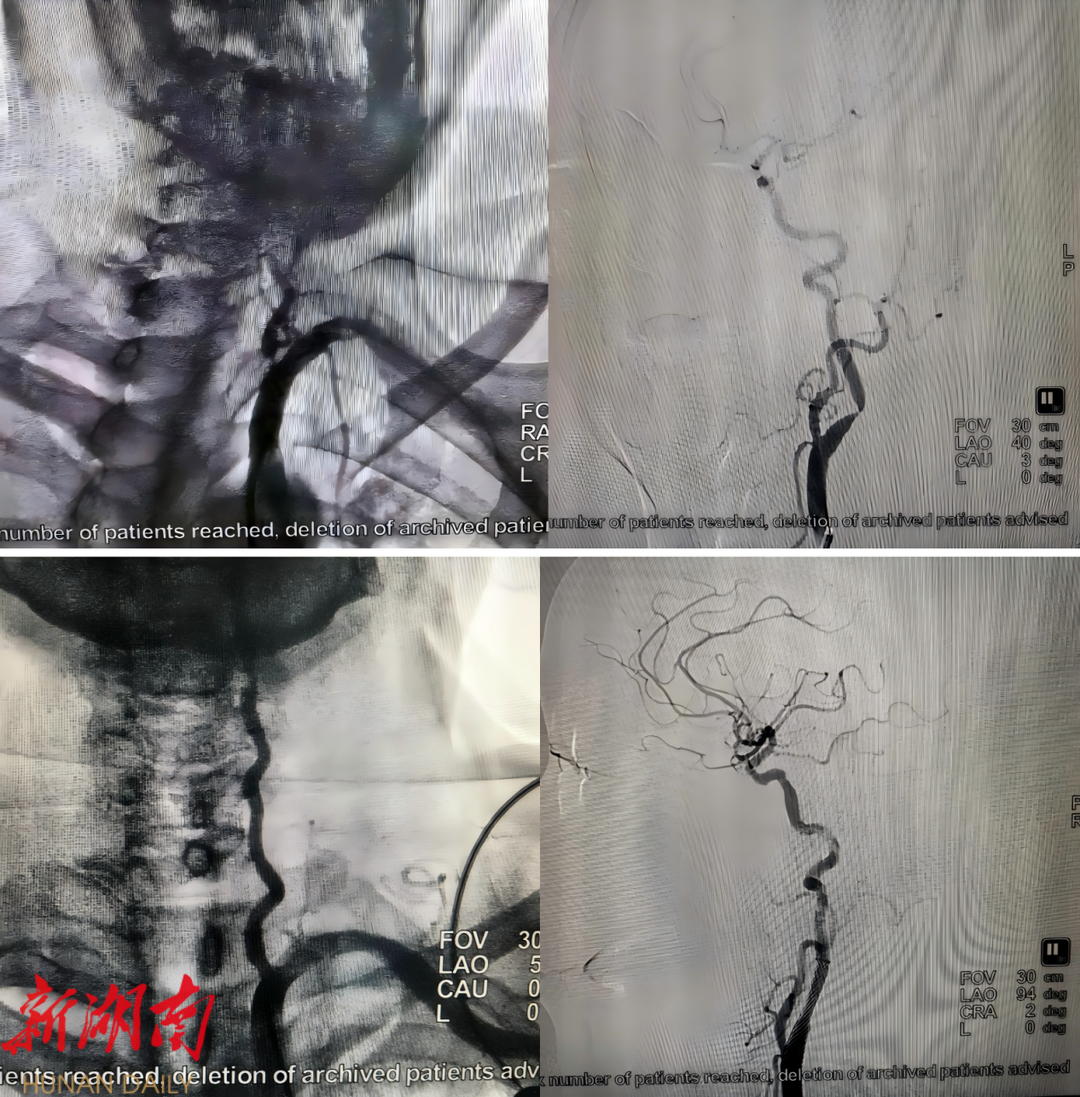

△术前(上)、术后(下)造影图像

然而,考虑到患者年纪尚轻且后循环梗死较为严重,医生们决定进一步为患者进行全脑血管造影术检查。检查结果显示,患者右侧椎动脉纤细,左侧椎动脉起始部存在重度狭窄,同时右侧颈内动脉闭塞,左侧颈内动脉起始部也存在重度狭窄。

在充分评估手术风险并与患者及家属详细沟通后,王灿医师带领新田县人民医院的神经介入团队,于11月12日成功完成了该院首例左侧椎动脉重度狭窄球囊扩张成形及支架置入术。手术仅用时不到2小时,术后患者左侧椎动脉的血流状况得到显著改善,症状完全缓解,行走基本恢复正常。随后,于11月27日,团队再次成功完成了左侧颈内动脉重度狭窄球囊扩张成形及支架置入术,患者术后恢复良好,现已康复出院。